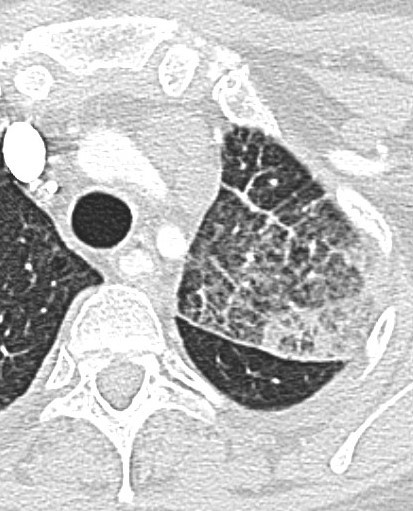

Round Atelectasis

Focal atelectasis with a round morphology that is always associated with an adjacent pleural abnormality (e.g. pleural effusion, pleural thickening or plaque, pleural neoplasm, etc). Round atelectasis is most common in the posterior lower lobes. All five of the following findings must be resent to diagnose round atelectasis: 1. Adjacent pleura must be abnormal. 2. Opacity must be peripheral and in contact with the pleura. 3. Opacity must be round or elliptical. 4. Volume loss must be present in the affected lobe. 5. Pulmonary vessels and bronchi leading into the opacity must be curved, this is the comet tail sign.